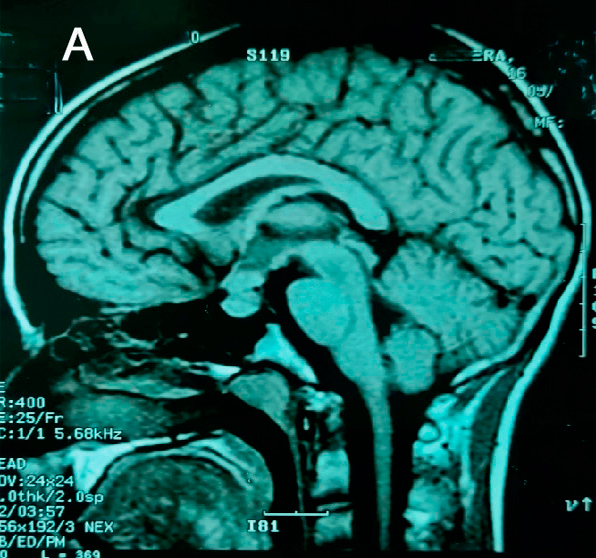

Se realiza diagnóstico de deficiencia de arginina-vasopresina central y se inicia desmopresina intranasal a demanda. Se realiza una RMN con enfoque selar, que reporta una lesión hipofisaria que compromete glándula y tallo hipofisario (Figura 1).

En lo endocrinológico, la afectación de la glándula hipófiisis se reporta en 5-50% de los pacientes con HCL, lo mas frecuente la deficiencia de arginina vasopresina en 50% de los casos7. Una minoría (5-20%) también presenta disfunción de hormonas de la adenohipófisis4,8,9. En la resonancia magnética nuclear (RMN) se puede encontrar a nivel de sistema nervioso central las siguientes manifestaciones: pérdida del punto brillante de la glándula pituitaria, engrosamiento del tallo pituitario >3 mm con realce, lesión masiva con isointensidad y realce homogéneo bajo imágenes potenciadas en T16.